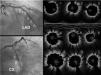

Case reportWe present the case of a 65-year-old male with nickel allergy who was admitted to the hospital with non-ST-elevation acute coronary syndrome. Coronary angiography showed significant two-vessel coronary disease not suitable for surgical revascularization because of small caliber and diffuse disease. There were multiple tandem lesions from the proximal to the distal left anterior descending (LAD) artery, bifurcated (Medina 1,1,1) with a diagonal branch, and a chronic total occlusion (CTO) in the mid circumflex (CX) (Figure 1).

The LAD was treated, first with predilatation with a 3.0 mm×20 mm non-complaint balloon in the distal LAD and the diagonal branch, and a 3.5 mm×20 mm balloon in the proximal LAD (balloon-scaffold ratio 1:1). Sequential and overlapping Magmaris scaffolds were then implanted (leaving 1 mm between the devices) from the distal LAD (one 3 mm×15 mm and two 3.5 mm×25 mm) to the bifurcation with the diagonal. StentBoost image enhancement (Philips) was used to adjust the overlap. Two more Magmaris scaffolds were then implanted in the median LAD (3.5 mm×25 mm) and the diagonal (3 mm×15 mm) by the reverse T and protrusion technique. The CTO of the CX was treated with a 3 mm×25 mm Magmaris. The scaffolds were implanted according to the manufacturer's recommendations to adequately predilate the lesion, select a device diameter very similar to vessel size, and postdilate without exceeding 0.6 mm above the nominal size of the device (Figure 1). In this case, we used non-compliant balloons with a 1:1 ratio except for the scaffold in the proximal LAD, which was postdilated with a 4.0 mm×20 mm non-compliant balloon. The final result was confirmed by OCT.

At three months, with no symptoms and with the patient's consent, coronary angiography was repeated (Figure 1). Three-month OCT showed appropriate strut apposition and partial covering of the majority of the struts (Figure 2).